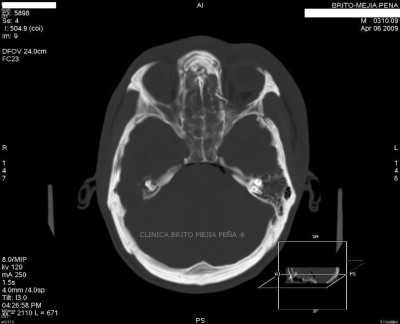

Fractura temporal